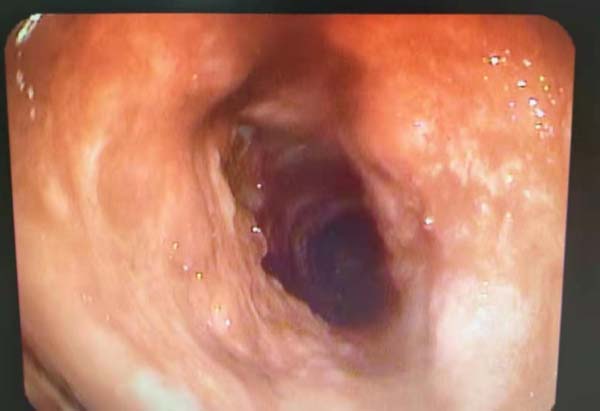

再通后的照片

经过以上治疗,患者终于能发声了。这个来自哈萨克族的老人开口说话后,喜极而泣,眼含热泪向周主任诉说着这些年求医的艰辛,表达着能再次开口说话时的喜悦!